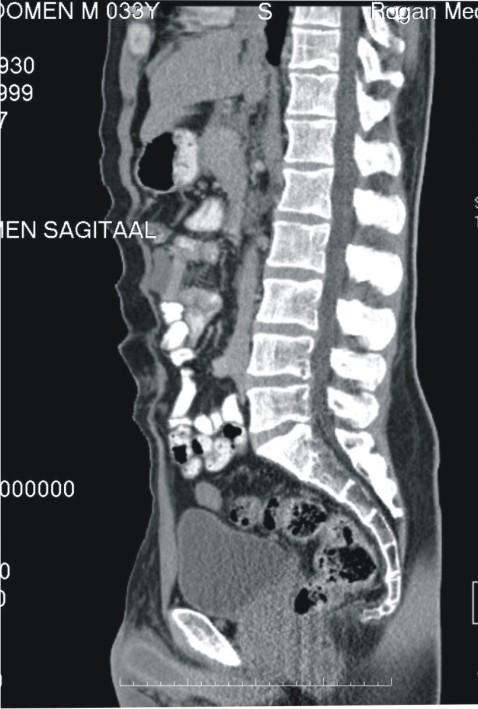

Panaromik görüntüler, çözünürlükleri bozulmadan büyütülerek ayrıntılı bilgiler elde ediliyor.

Çözüm PACS, merkezi veri tabanında bilgilerin depolanması ile oluşan sayısal arşiv (görüntüler üzerinde işlem yapmaya izin verecek şekilde yüksek çözünürlükte saklandığı için ölçüm ve tanıya ilişkin işlemler kolaylıkla yapılabiliyor), bilgilerin yeniden kullanılmasını arşivlenen bilgilerin modern tanı yöntemleri ile incelenmesini sağlıyor.

Sayısal görüntüler üzerinde işlem ve ölçüm yapılabiliyor. Görüntüler ve raporların her an, her yerde (tüm iş istasyonları üzerinden sorgulama yapılarak) ulaşılabilir olmasına ve görüntü işleme ve ölçüm (mesafe, açı, uzunluk, yoğunluk) yapılabilmesine olanak sağlıyor.

Radyoloji uzmanlarının tanı süreçlerinin sonuçlanmasında ve doğruluğunda en büyük yardımcı etken Çözüm PACS oluyor [sayısal olarak elde edilen panoromik görüntüler, çözünürlük bozulmadan büyütülüp, belirli bir noktaya odaklanarak, daha detaylı bilgiler elde ediliyor, görüntülerin herhangi bir yerine yazı veya şekil yerleştirmesi ve seçilen görüntünün fare kontrolünde yer değiştirmesi (pan) ve tam ekran incelemesi mümkün oluyor.] İncelenen görüntüler istenildiğinde DICOM yazıcılara gönderilerek film olarak basılabiliyor.

Sayısal görüntülerin ayrı ekranlarda karşılaştırılmasını (yan yana iki çalışma şeklinde, yatay ya da dikey olarak bölünmüş, ters çevirilmiş vb.) sağlayarak, zaman içinde oluşan değişikliklerin değerlendirilmesine, (önceki verilerle karşılaştırma) konsültasyon olanaklarının artırılmasına yardımcı oluyor.